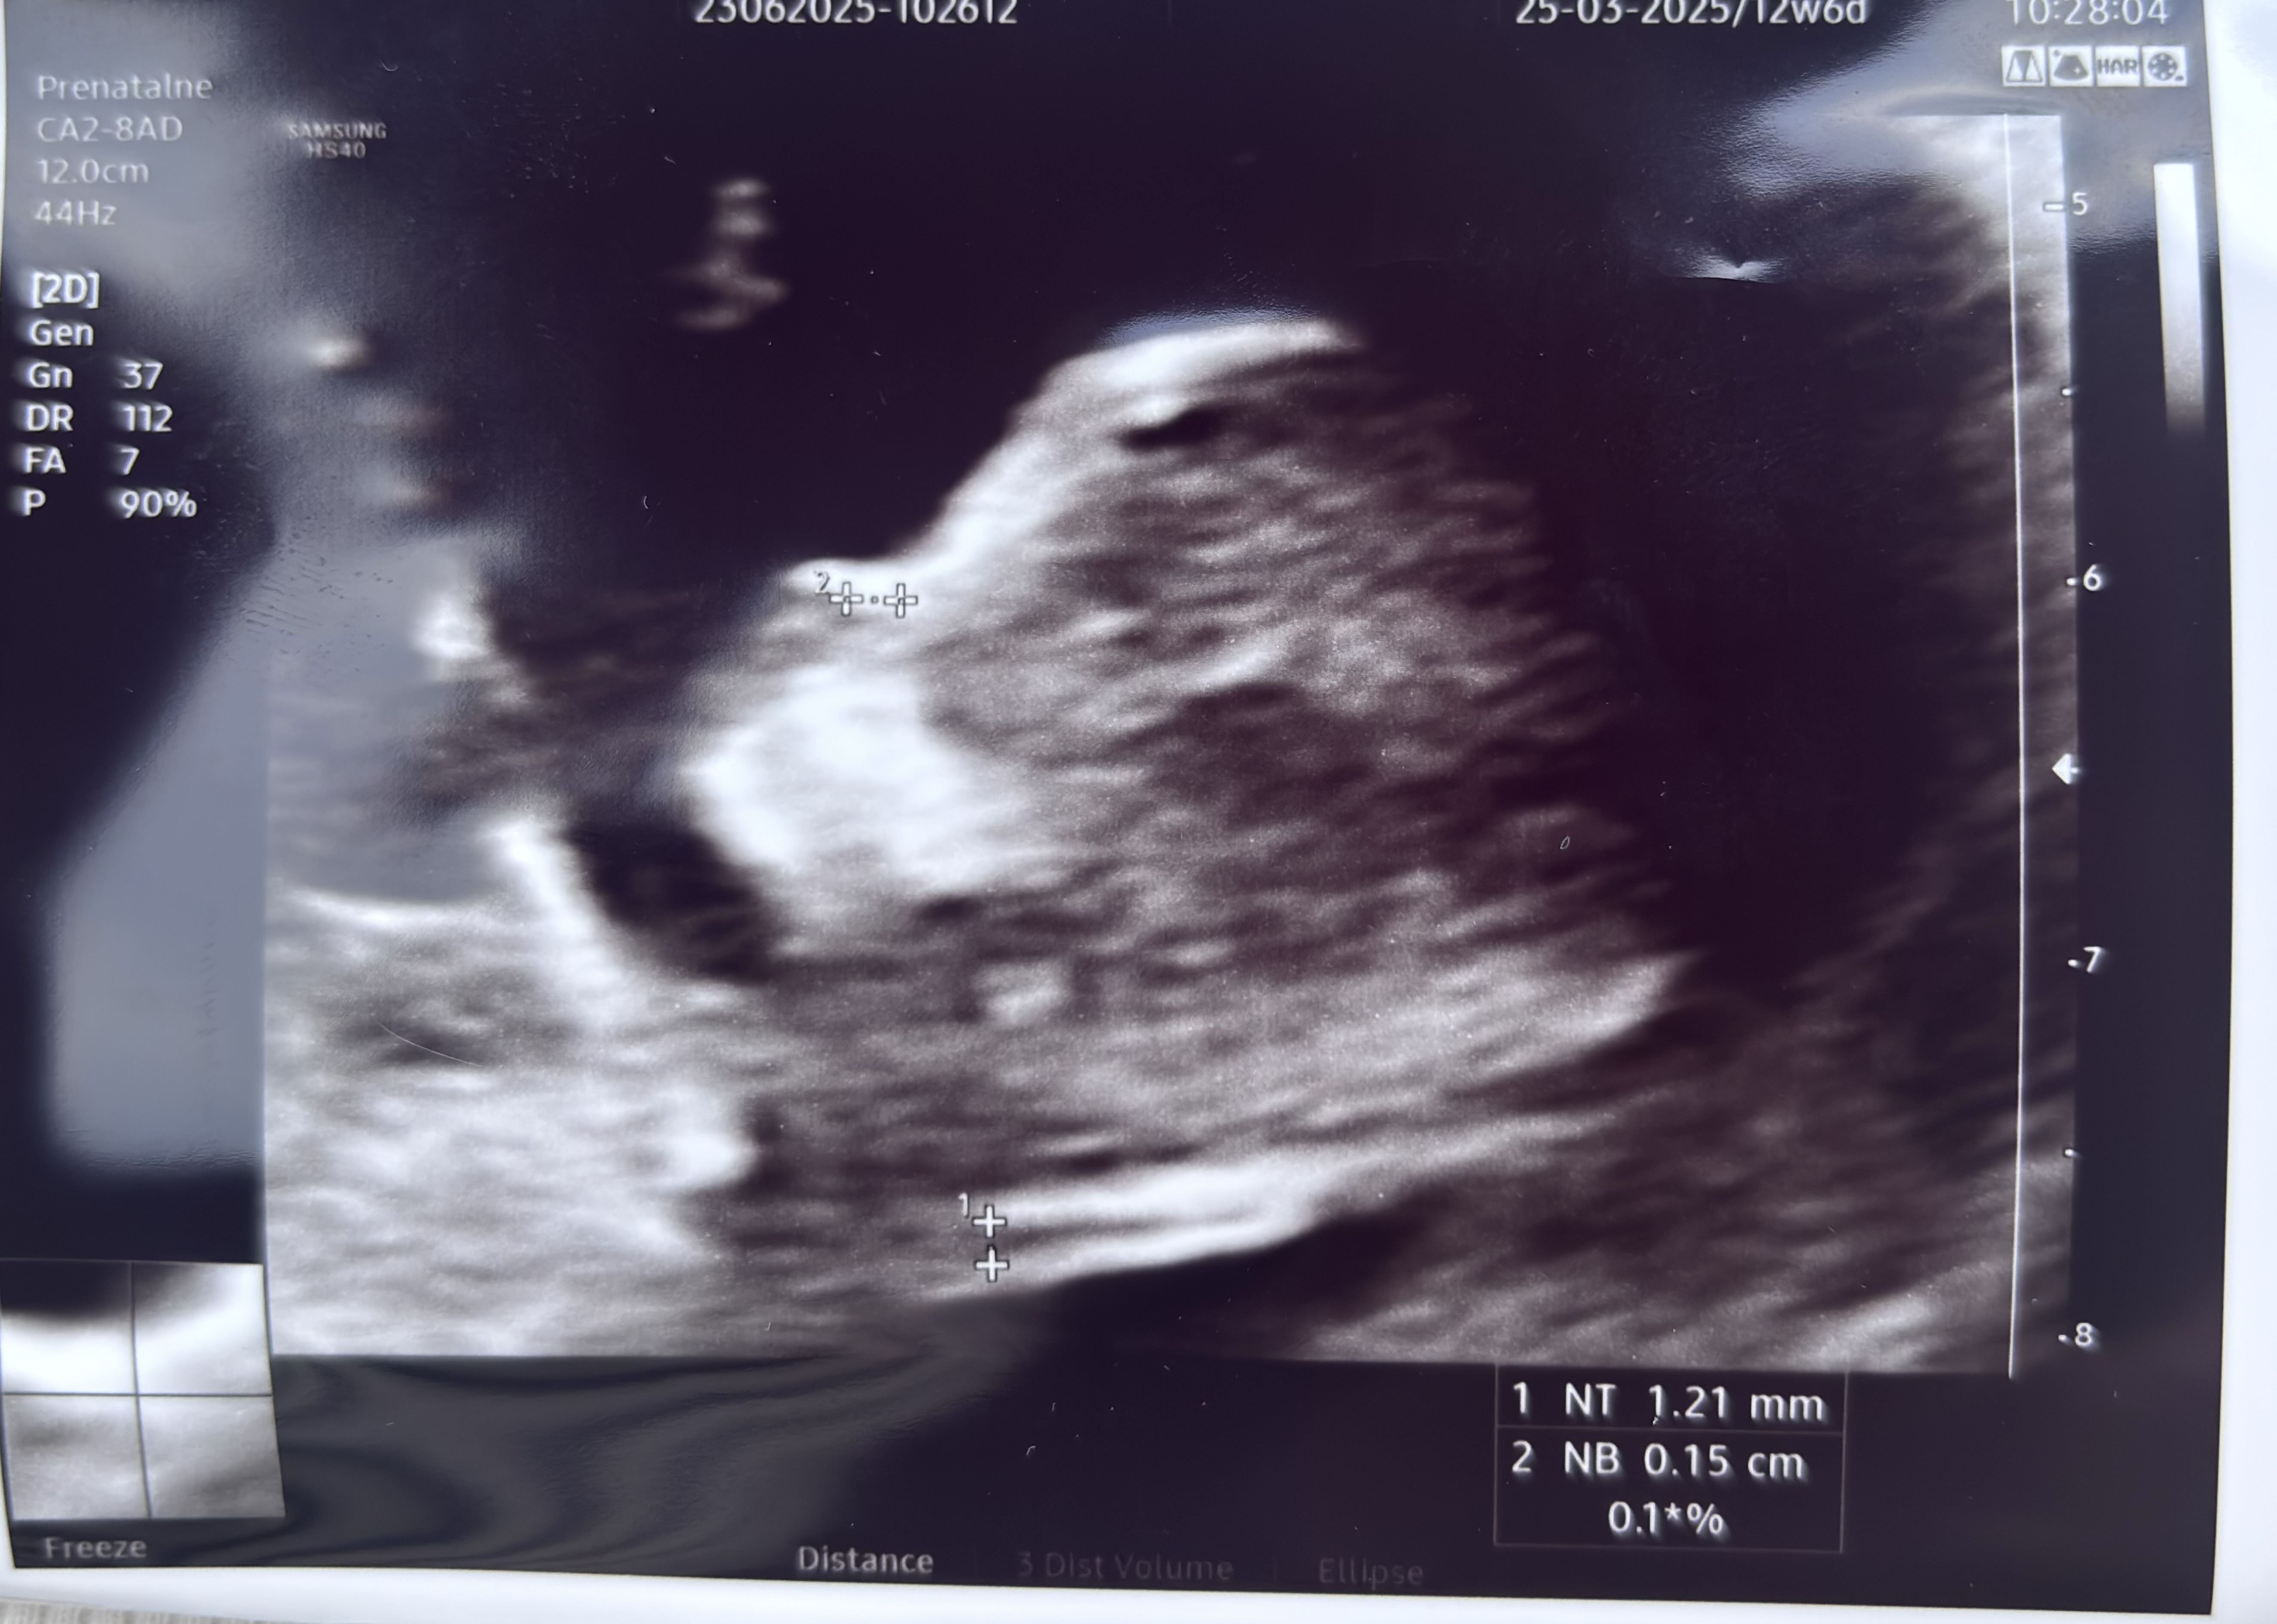

Cudowne wieści, gratulacje @SzklanaKulka i @anusia87, piękne dzidziusieTo i ja swojego bejbuna pokaże! A co![]()